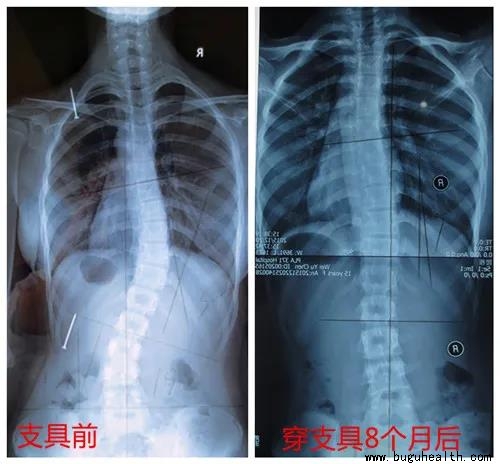

不戴支具与戴支具对比:

如图所示,从左到右看,度数从腰左弯18°矫正到腰右弯5°,中线左边的椎体在支具内矫正到中线右边。度数和中线都过矫,这是带上支具最理想的结果不过,大部分孩子很难实现双过矫。当双过矫不能实现时,先实现中线过矫,度数尽量减少。